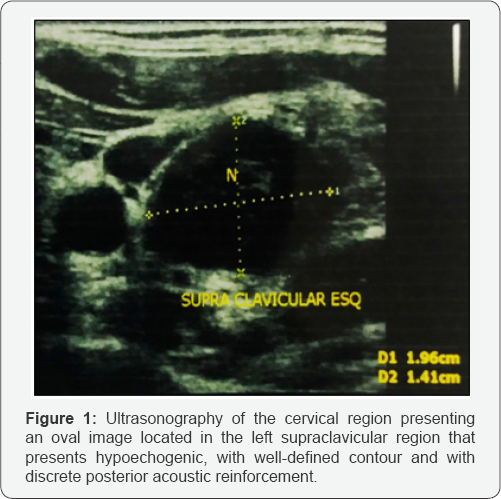

Ultrasonography of the cervical region showed the presence of two oval images. These lesions were hypoechogenic, with a well-defined contour that had a slight posterior acoustic reinforcement and were located in the left supraclavicular region, the first one, measuring 2.4 x 1.6 cm and the second, measuring 2.0 x 1.4 cm (Figure 1).